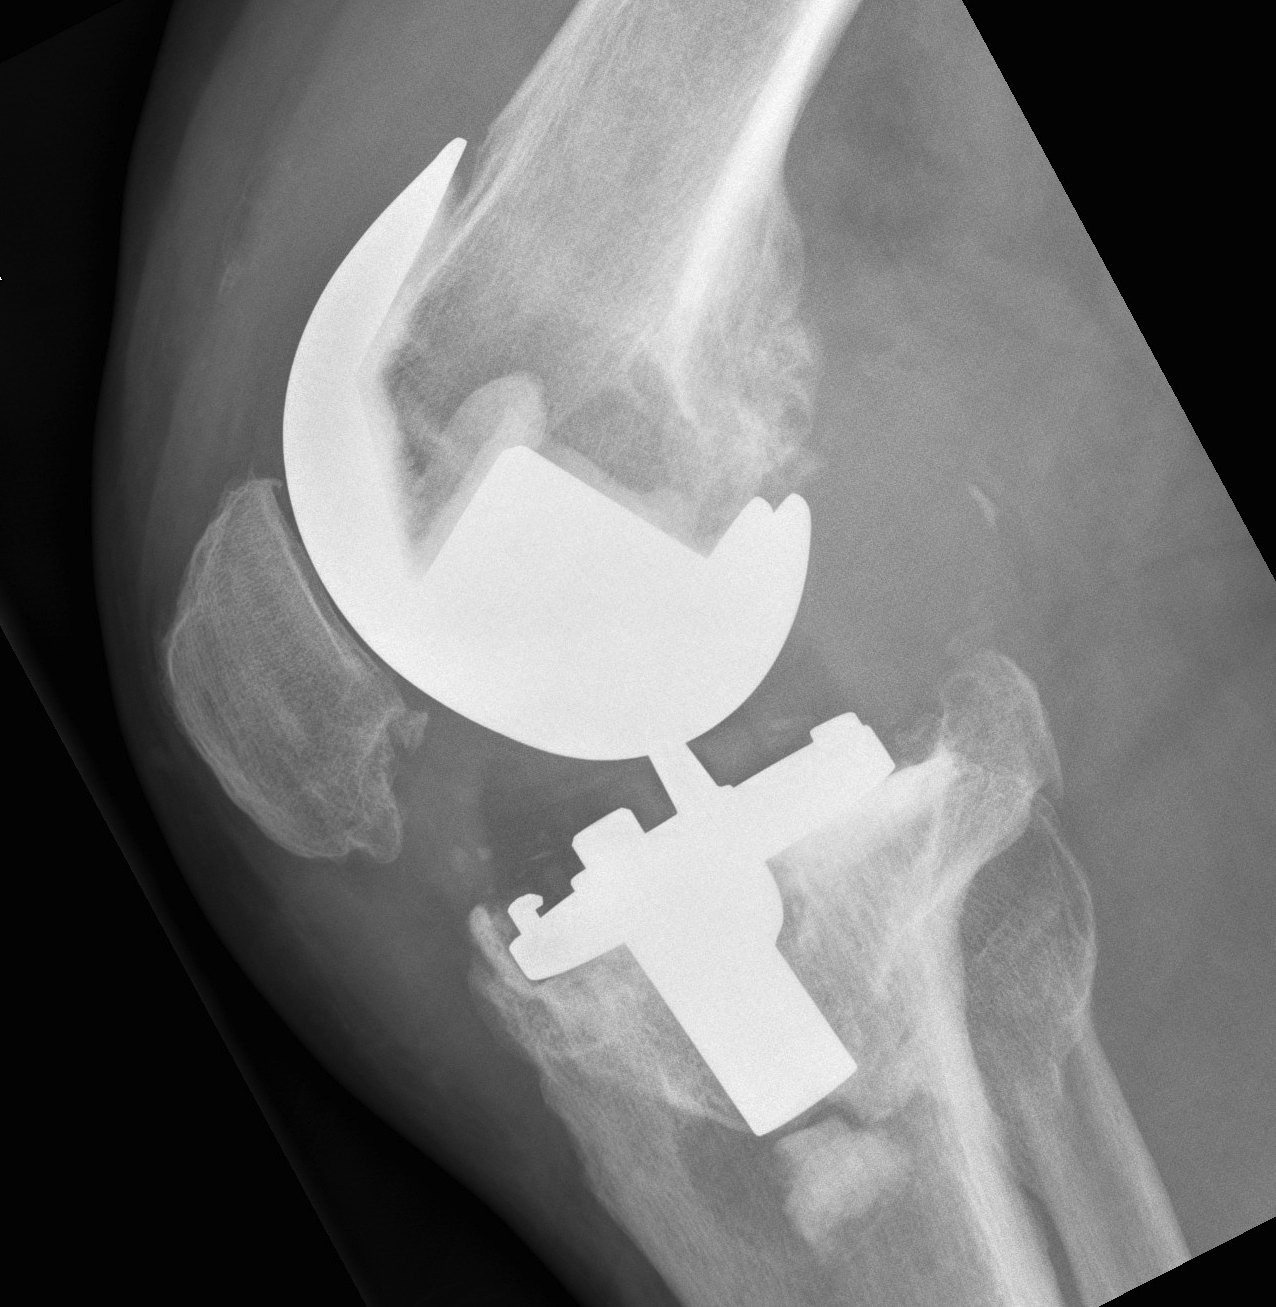

2. Anterior tibial slope

Due to incomplete posterior osteotomy closure

- need to be aware

- ensure correct slope with bone cuts